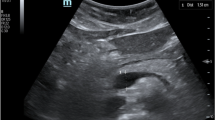

The ultrasound scanning protocol, in sequence, included four views with seven images: parasternal long axis 2D with and without color-flow Doppler over the mitral and aortic valve simultaneously, apical 4 chamber 2D with and without color-flow Doppler over the mitral valve, apical 4 chamber 2D with color-flow Doppler over the tricuspid valve, apical 5 chamber 2D with and without color-flow Doppler over the aortic valve, and subcostal view of the inferior vena cava with sniff. To facilitate reproducibility trainees were taught to obtain views in the pre-specified sequence during each patient exam. Views were selected to identify a predetermined set of six key pathologies, namely left ventricular (LV) dysfunction, pericardial effusion, aortic valve regurgitation, moderate to severe mitral valve regurgitation, moderate to severe tricuspid valve regurgitation, and mitral valve stenosis. A subjective assessment of LV function was based on visual estimation of an ejection fraction (EF): > 50% indicating normal LV function and < 50% indicating LV dysfunction. The LV functional assessment was determined using the parasternal long axis and apical 4 and 5 chamber views. The presence of pericardial effusion was documented regardless of size. Pericardial effusion was assessed using the parasternal long axis and apical 4 and 5 chamber views. Assessment of valvular dysfunction was done utilizing qualitative assessment. With regard to regurgitation, subjective vena contracta width and jet area occupying the respective atria (left atrium for mitral regurgitation and right atrium for tricuspid regurgitation) were utilized. Mitral valve regurgitation was assessed using the parasternal long axis view with color Doppler and the apical 4 chamber view with color Doppler over the mitral valve. Tricuspid regurgitation was assessed using the apical 4 chamber view with color Doppler over the tricuspid valve. Aortic regurgitation was assessed as being present or absent; grading of aortic regurgitation was not performed. The presence of aortic regurgitation was assessed using the parasternal long view with color Doppler and the apical 5 chamber view with color Doppler over the aortic valve. A subjective assessment for mitral stenosis was used, including the presence of subjective thickening and restricted motion of the mitral leaflets and color Doppler demonstrating flow acceleration across the mitral valve. Mitral stenosis was only assessed as present or absent, and grading of severity was not preformed. Assessment of mitral stenosis utilized the parasternal long axis view with and without color Doppler over the mitral valve and apical 4 chamber with and without color Doppler over the mitral valve. Didactic and practical sessions used both English and Kiswahili languages.

The percentages of images, by scanning view, that were determined by the cardiologists to be of sufficient quality (grade 3 or higher) for interpretation were as follows (Fig. 1a): parasternal long axis 2D 86.9%; parasternal long axis with color Doppler 82.0%; apical 4 chamber 2D 75.0%; apical 4 chamber with color Doppler 77.3%; apical 5 chamber 2D 69.9%; apical 5 chamber with color Doppler 69.4%; subcostal 2D 56.8%. The percentages of scans that were determined by the cardiologists to contain appropriate images of sufficient quality for interpretation as to whether key pathologies were present or absent were as follows: (Fig. 1b): pericardial effusion 89.9%; LV dysfunction 87.3%; aortic regurgitation 85.1%; mitral valve regurgitation 88.9%; tricuspid valve regurgitation 82.4%; presence of mitral valve stenosis 91.8%. By trainee, the overall percentages of images that were determined by cardiologists to be of grade 3 or higher quality ranged from 18.0% (29/161) to 94.2% (356/378), median 76.7%; 5 of 8 trainees achieved 75% or greater interpretable images (Fig. 2a). Score on the post-training 20Q Ultrasound Images assessment (p = 0.004) and number of ultrasound examinations performed prior to study training (p = 0.039) were each positively associated with image quality in univariate analyses (Table 2).